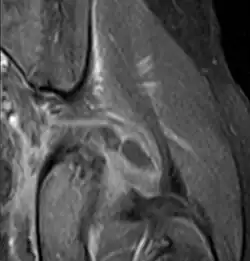

Axial T1 weighted fat suppressed post IV gadolinium contrast enhanced MRI image showing a mutliloculated bacterial abscess in the left gluteal muscle which grew Staphylococcus aureus (methicillin sensitive) thought to be due to tropical pyomyositis.